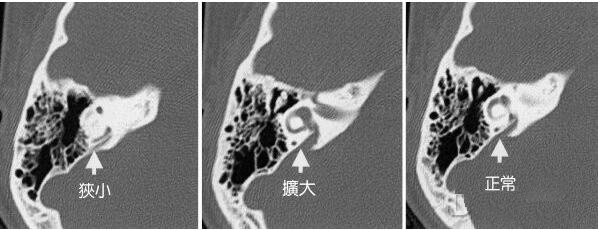

诊断主要依据高分辨CT和MRI,颞骨CT扫描为主要放射学检查方法。

感觉声音的主要结构-内耳,由骨迷路和膜迷路组成,膜迷路内有内淋巴液,内淋巴液的正常代谢对维持正常的听力是密切相关的,前庭导水管将膜迷路与内淋巴囊相连,而正常大小的前庭导水管是维持内淋巴液代谢所须的。由于先天发育异常导致前庭导水管扩大时,内淋巴液可经扩大的前庭导水管从内淋巴囊倒流于耳蜗或前庭,损伤感觉毛细胞出现耳聋或眩晕。